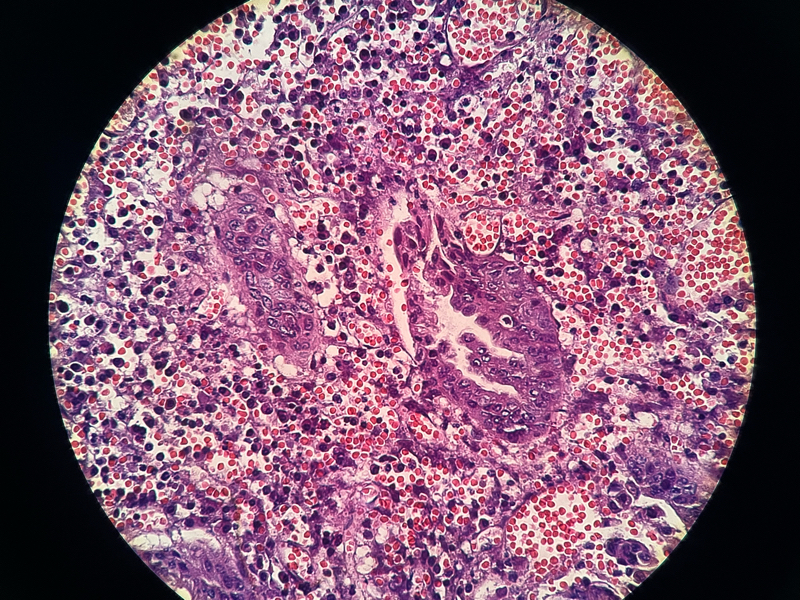

性别

女

年龄

54

临床诊断

急性阑尾炎

一般病史

持续性右下腹痛8小时

标本名称

阑尾

大体所见

阑尾约7.1cm ,直径约1.0-1.2,局部有脓苔

请各位老师看下这有没有问题,担心漏诊

化脓性阑尾炎。